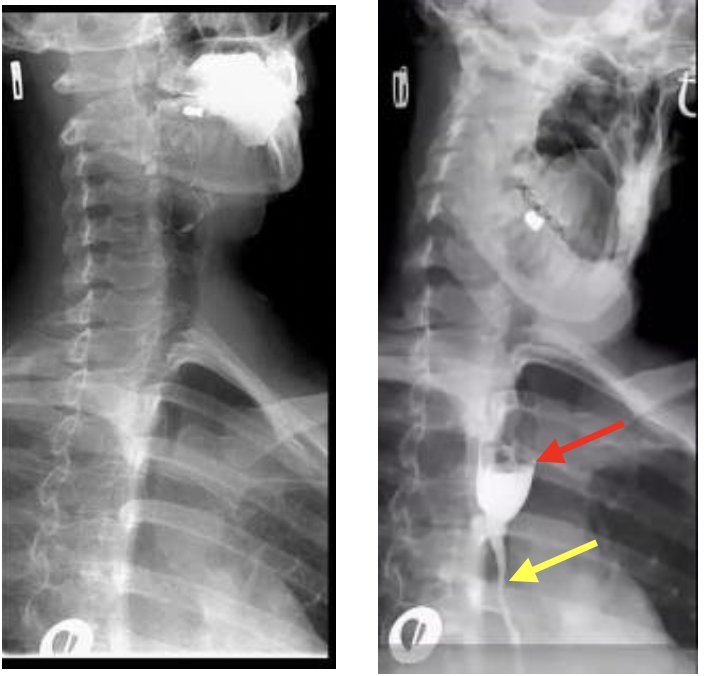

נותנים חומר ניגוד לוריד, בדוגמה הזו למשל מסתכלים על קנה הנשימה, מסתכלים על החומר בכלי הדם סביבו, לאחר כמה שניות רואים שחומר הניגוד פרץ את הוושט (יציאה של חומר הניגוד באופן לא תקין)

Comb’s sign מהו?

א]שר לראות עיבוי של דופן המעי הדק (חץ אדום),

Comb’s sign גודש של כלי הדם המזנטריאלים שמספקים את הלולאה החולה, מסומן בחץ ירוק.